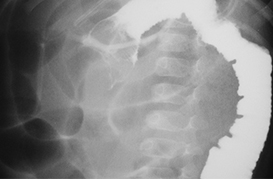

Cuerpo Extraño en Esofago